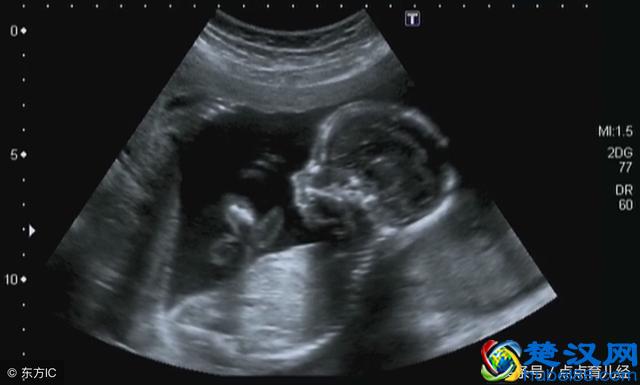

4、四维彩超比三维彩超更优势的地方是它可以呈现动态的图像,你不仅可以直观的看到宝宝的样貌,还可以看到某一瞬间宝宝活动的情景,吃手、吐羊水、蹬腿、捂脸这些动作可以通过四维彩超表现出来。

3、三维彩超相比B超、彩超有了质的飞跃,因为它是彩色的、三维立体的,你可以通过图像看清楚肚子里面的宝宝长什么样。